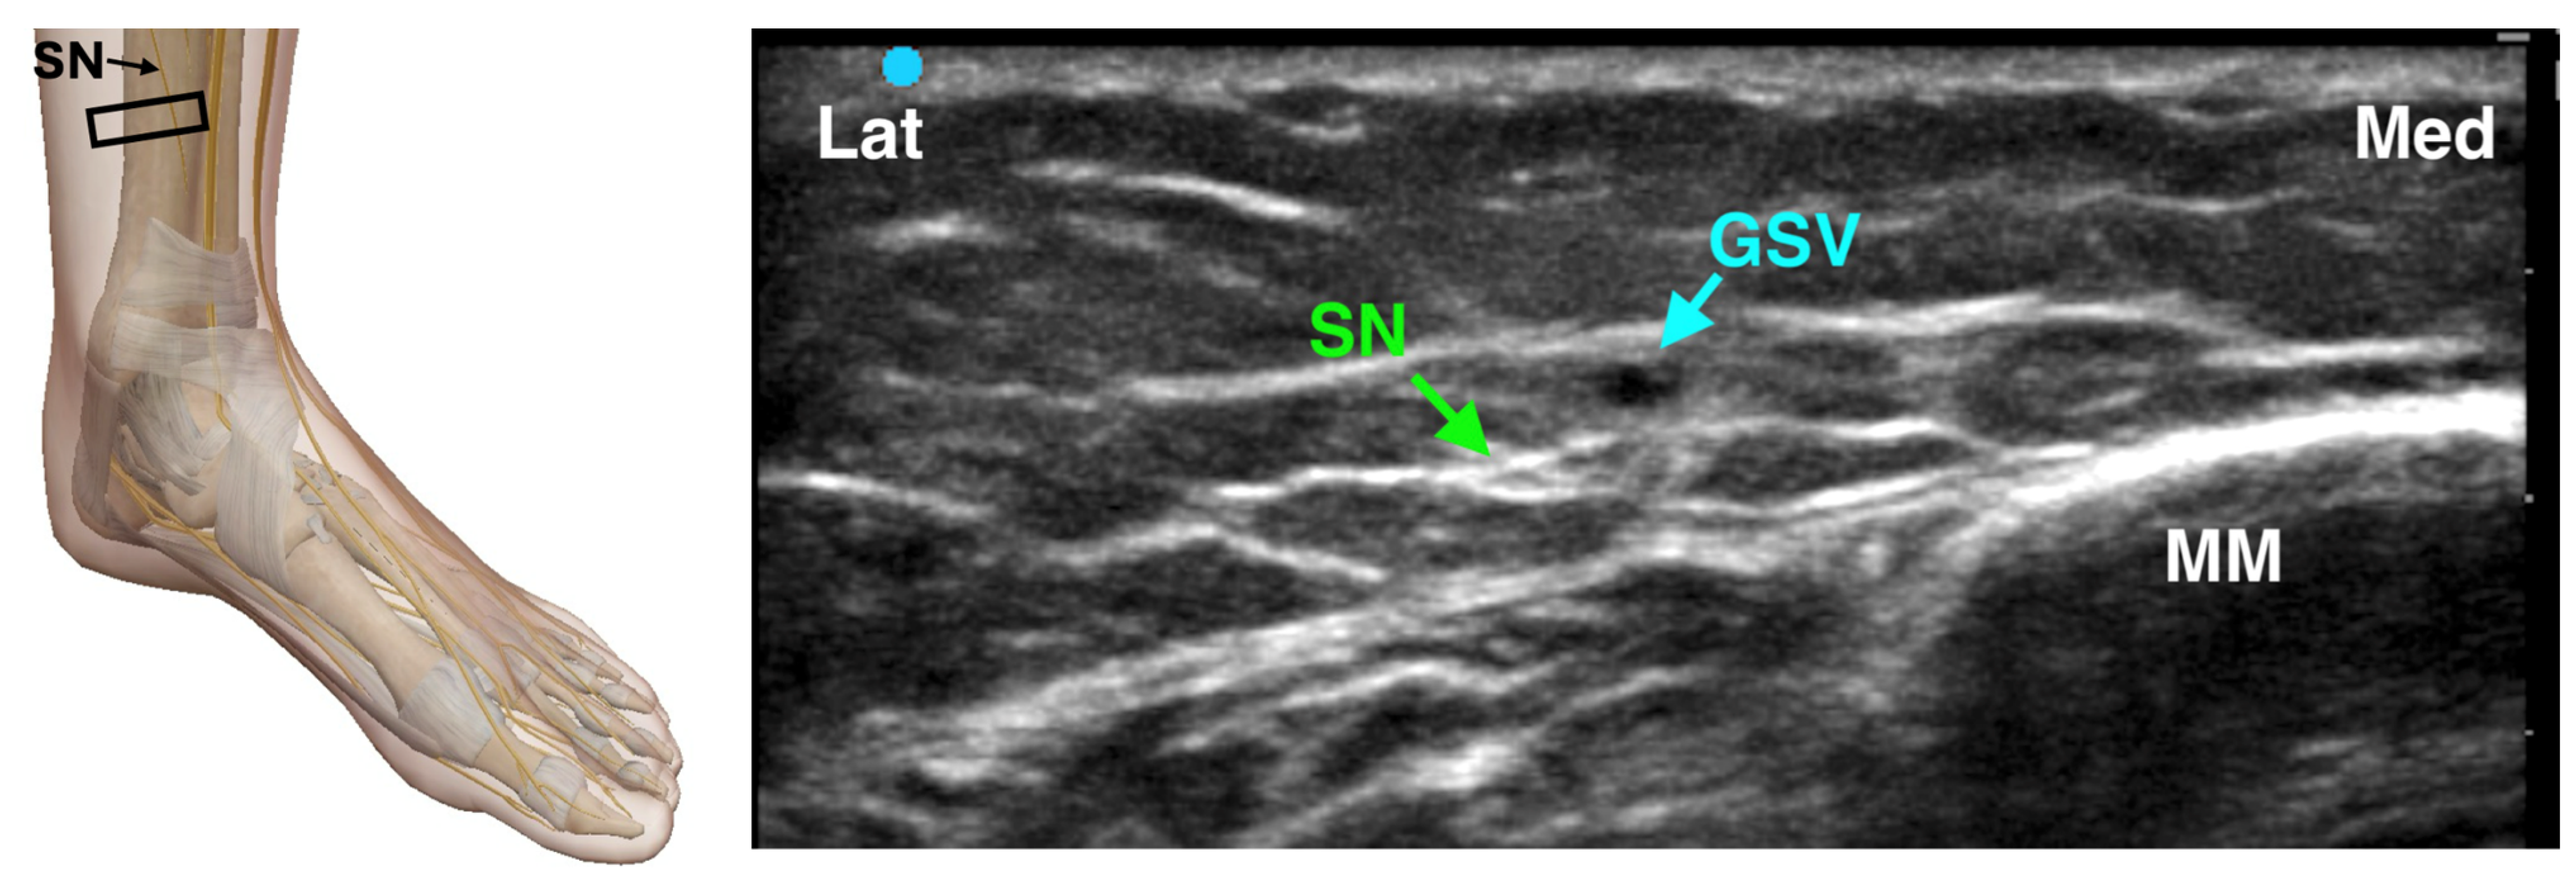

4.3.4. Saphenous Nerve Block

The saphenous nerve is a purely sensory branch of the femoral nerve that provides innervation to the medial aspect of the ankle and foot. It runs in close proximity to the great saphenous vein, offering a useful vascular landmark for nerve localization. In the landmark-based technique, a semicircular subcutaneous injection of 3–5 mL of local anesthetic is administered approximately 2 cm above the medial malleolus, on either side of the great saphenous vein, which serves as the primary reference point. For an ultrasound-guided approach, the probe is positioned anterior to the medial malleolus in a transverse plane to visualize the nerve adjacent to the vein (Figure 6). The saphenous nerve may appear either superficial or deep to the great saphenous vein, and a perivascular injection is used to ensure effective anesthesia. Given its superficial location, a field block technique is often appropriate. The need for a saphenous nerve block depends on the planned surgical procedure: it is particularly relevant for proximal osteotomies but is generally unnecessary for more distal foot surgeries [29].

Figure 6. Ultrasound-guided Saphenous Nerve Block. SN: Saphenous Nerve; GSV: Great Saphenous Nerve; MM: Medial Malleolus; The black rectangle indicates the placement of the ultrasound probe on the anatomical area.